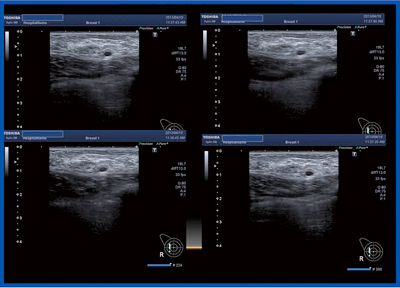

超音波検査では,広範囲に低エコー域が認められ,病変の同定,範囲が難しい症例であった(図11)。このような症例に対し,正常乳腺エコーの画像と対比するため,新プローブPLT-1005BTは有用であった(図12)。病変部位の同定が確実になり,範囲診断も可能となった。

エラストグラフィでは,正常乳腺と病変部が一目でわかる画像が得られた(図13)。4か所に6mmの浸潤癌が認められ,広範な管内の進展がある病変であった。管内病変が膨れてくると,硬さとして表現されると考えられる。

図12 症例6:PLT-1005BTプローブを用いたBモード画像

図13 症例6:エラストグラフィ(a)

b:Bモード画像,c:病理組織像